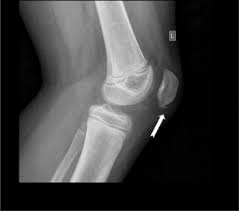

2 Sinding Larsen Johansson Syndrome Slj An 11 Year Old Male With 1 Download Scientific Diagram